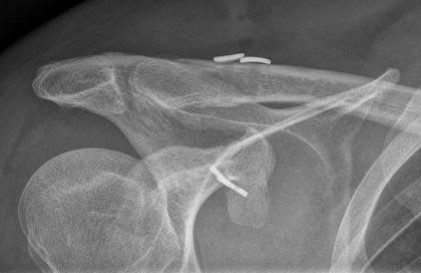

Haben die radiologischen Untersuchungen eine Arthrose des Schultergelenkes ergeben, wird diese zunächst mit konservativen Mitteln und gelenkerhaltenden Maßnahmen therapiert. Hierzu zählen unter anderem die minimal-invasive Arthroskopie, also die Gelenkspülung und Knorpelglättung, und die Knorpelzelltransplantation bei Verletzungen des Knorpels.

Ist der Verschleiß des Gelenks weit fortgeschritten, ist das Einsetzen eines künstlichen Gelenks, einer sogenannten Endoprothese, erforderlich, um die Beweglichkeit wiederherzustellen und Schmerzen zu lindern. Weitere Gründe für den Einsatz einer Endoprothese sind komplexe Brüche des Oberarmknochens oder der Gelenkpfanne, komplexe Sehnenverletzungen (Rotatorenmanschettenrupturen) sowie unfallbedingte, rheumatisch und tumorbedingte Gelenkschäden. Je nach individuellem Krankheitsbild werden verschiedene Prothesenarten verwendet. Diese sind aus besonders gut verträglichen Materialien wie zum Beispiel Titan gefertigt und zeichnen sich durch eine lange Haltbarkeit aus. Patienten profitieren außerdem von einem verkürzten Genesungsprozess, da Kunstgelenke im Cellitinnen-Krankenhaus Maria-Hilf besonders schonend eingesetzt werden. Hierfür werden minimal-invasive Operationsverfahren genutzt, bei denen Muskeln und Sehnen nicht durchtrennt, sondern lediglich beiseitegeschoben werden. Folgende Arten des Schultergelenkersatzes bietet die Orthopädie des MHK so an: